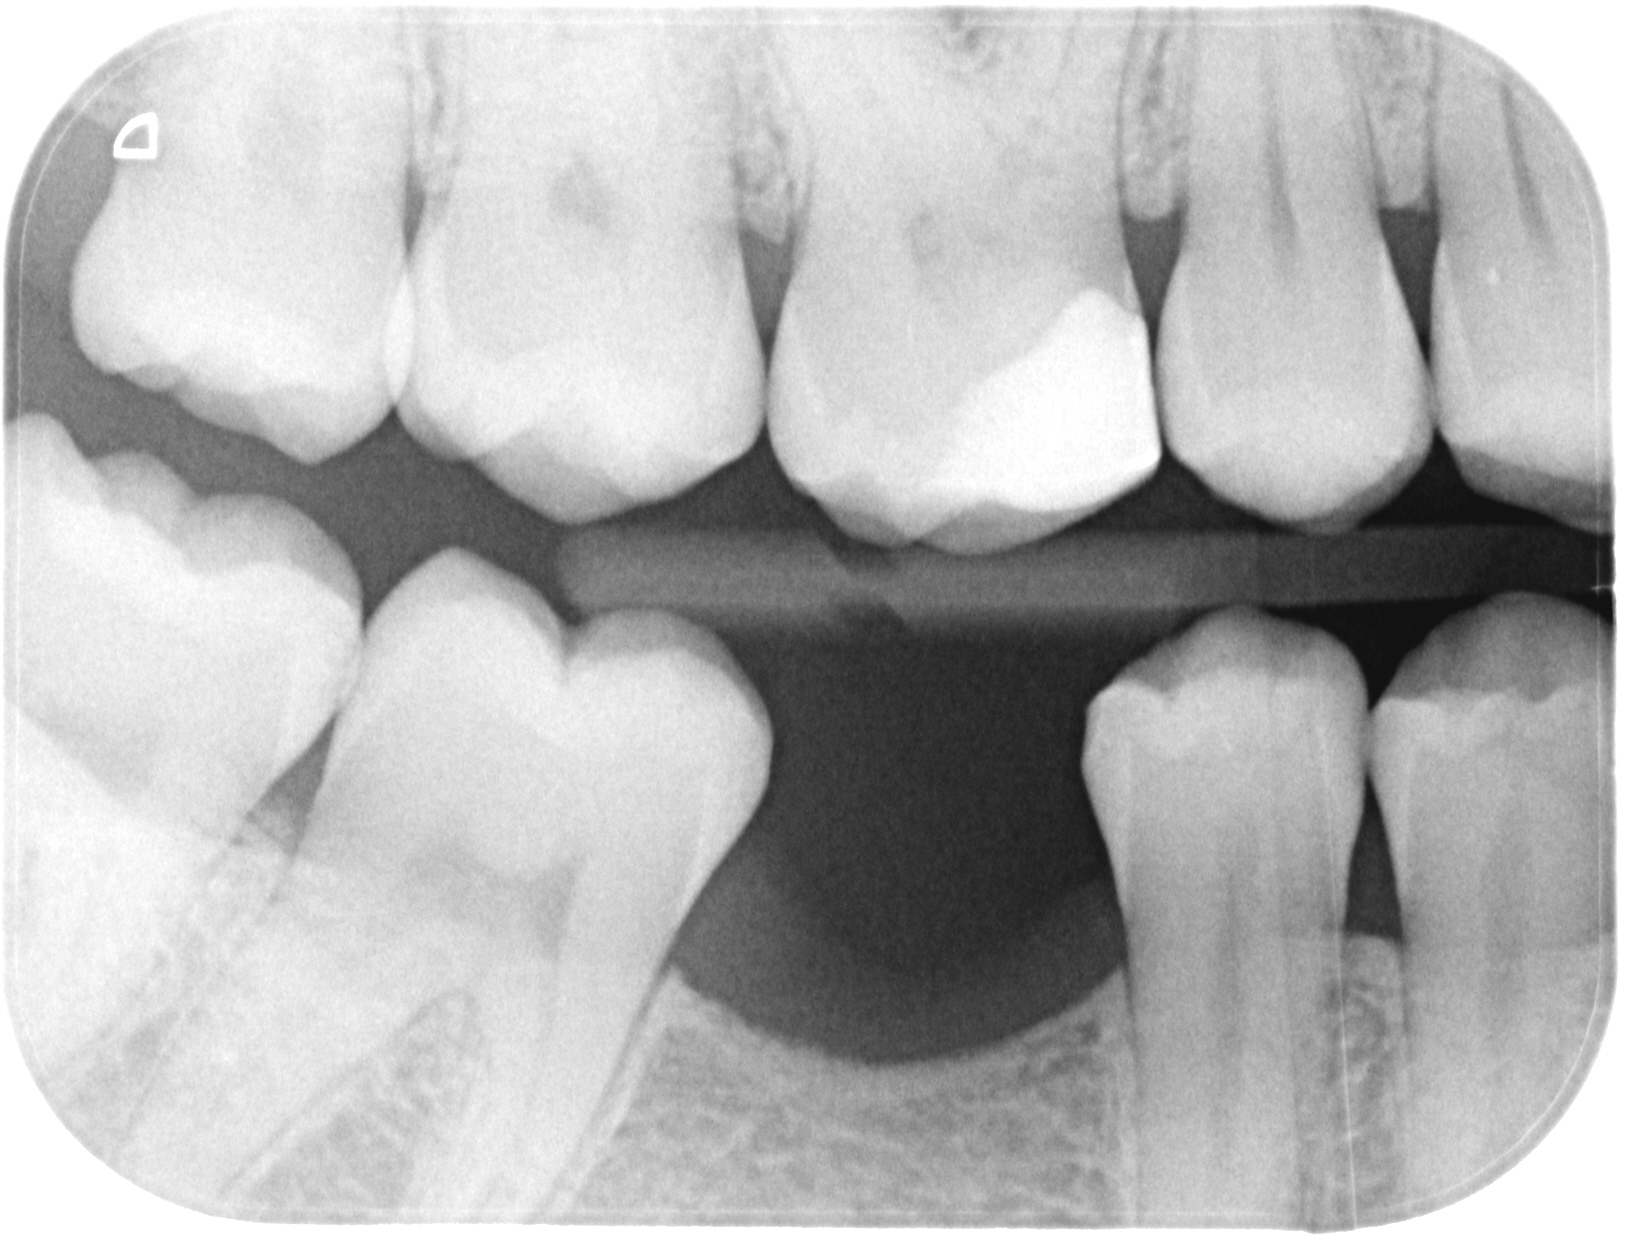

Bitewing X-ray